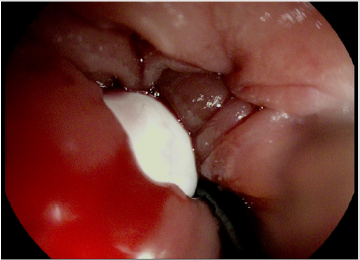

The patient swallowed the capsule (Pillcam SB3, Medtronic) smoothly without real-time monitoring. The capsule recording was examinated on the following day, and showed persistent esophageal mucosa images, so it was suspected to be stuck in a Zenker diverticulum. The patient was asymptomatic, but he was unable to report capsule excretion. A neck radiograph was performed, showing a radiopaque foreign body, compatible with the capsule, retained in the patient’s neck. Due to the risk of a spontaneous expulsion of the capsule in the upper airways, it was decided to remove it. The patient underwent upper endoscopy, and the capsule was extracted after several efforts (Figures 1 & 2). On the subsequent days the patient had an uneventful course and was discharged in stable clinical conditions.